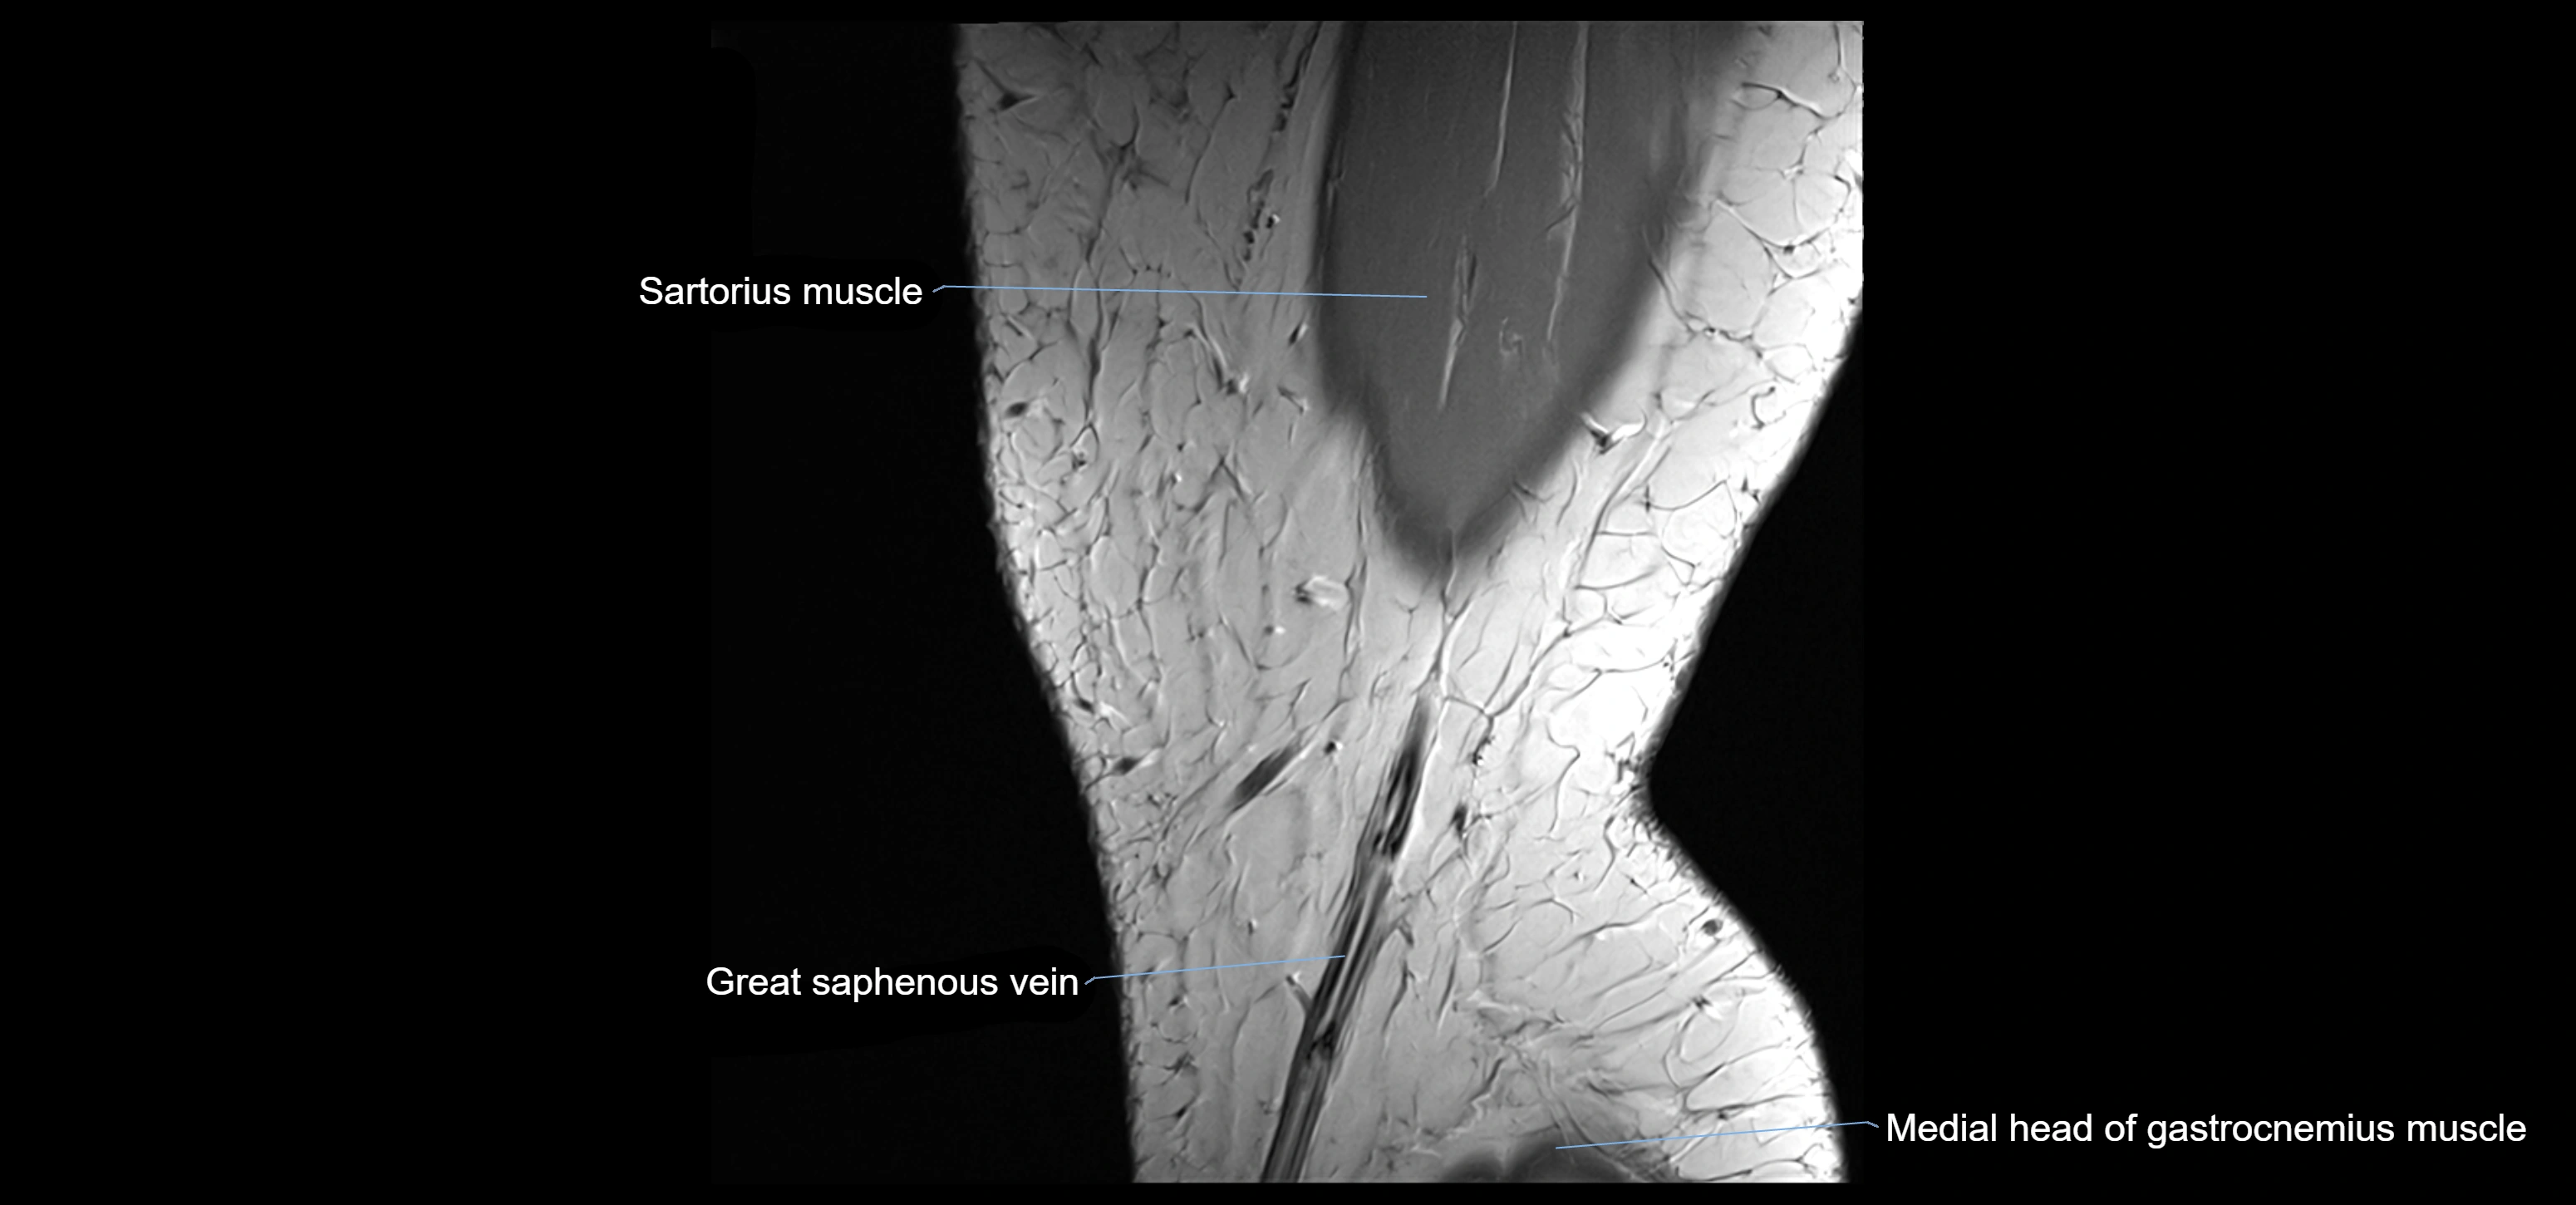

- Sartorius muscle

- great saphenous vein

- Medial head of gastrocnemius muscle